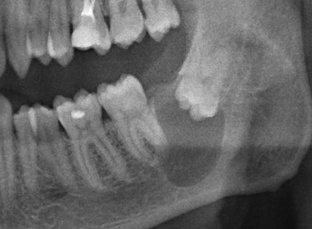

История Александра находится здесь>>, и мы очень рекомендуем её прочитать. Для вашего удобства мы не перепечатываем её вновь. Вместо этого, мы выбрали из неё достойные пояснения и ремарок цитаты: они выделены вот таким образом и снабдили их уместным, на наш взгляд, комментарием. Пользуясь случаем, мы еще раз благодарим Александра, за прекрасное и честное описание своего лечения , а также предоставленную возможность дать к нему пояснения. *    *    * В 16 лет я увидел панорамный снимок (фото ниже)...